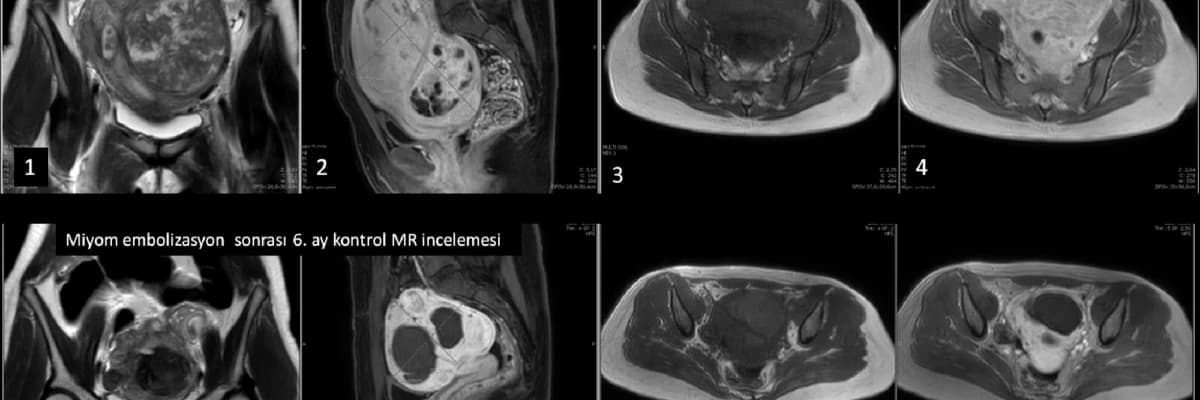

MİYOM EMBOLİZASYONUN DOĞURGANLIĞA ETKİSİ NEDİR?

Miyom tedavisinde girişimsel radyoloji önemli bir rol oynamaktadır. Uzun yıllardan beri embolizasyon güvenilir bir miyom tedavi yöntemi olarak uygulanmaktadır. Embolizasyondan sonra hamile kalan ve normal doğum yapan bir çok kadın bildirilmiştir. Dolayısıyla, miyom embolizasyon tedavisinin genel olarak gebe kalmaya ve sağlıklı doğum yapmaya bir engel oluşturmadığı gösterilmiştir. Ancak embolizasyon işlemi sırasında çok düşük olasılık olsa da yumurtalıklara ve rahime kalıcı hasar verme riski mevcuttur. Bu konuda halen devam eden bir çok bilimsel çalışma yapılmaktadır. Özellikle miyom embolizasyon ve miyomektomi sonrası hamilelik oranları bir çok çalışmada karşılaştırılmıştır. Bazı çalışmalarda miyomektomi sonrası hamilelik oranları bir miktar daha yüksek bildirilmiş olsa da sonuçlar arasında ciddi sapmalar mevcuttur. Miyom embolizasyonu sonrası hamilelik oranları miyomektomiye yakın olarak bulunan çalışmalar da bildirilmiştir.

Güncel bilgilerimize göre, gelecekte mutlaka gebelik isteyen ve tekli miyomlara sahip genç kadınlarda, miyom tedavisi için ilk seçenek miyomektomi olsa da cerrahi istemeyen hastalarda miyom embolizasyonu önemli bir alternatiftir. Gebeliği mutlak koşul olarak görmeyen hastalarda ya da miyomektomiye uygun olmayan çok sayıda miyom içeren hastalarda embolizasyon tedavisi öncelikle tercih edilmelidir.